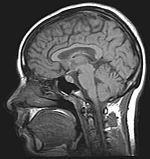

Obrázky röntgenových snímkov (vpravo srdce, vľavo hlava)